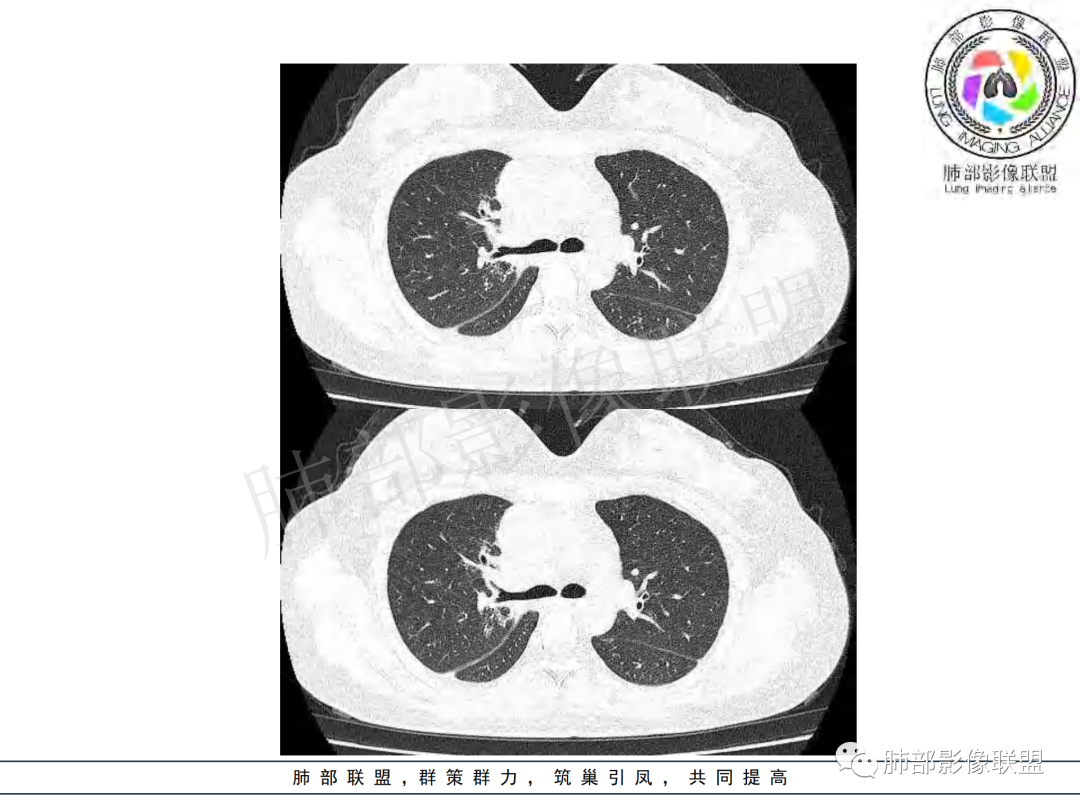

纵隔多组及右侧肺门多发肿大淋巴结,部分融合,不均匀强化,内见斑片状坏死区及环状强化,后者坏死边界尚清晰,肺门区肿大淋巴结与肺组织边界不清,年轻女性,8个月病史,发热首发症状,考虑淋巴结核并向肺内侵及(破溃?),鉴别淋巴瘤

女,20,病程长达8月,发热、胸痛、右侧胸腔积液病史。胸部CT:右肺门旁不规则肿块影,右中间支气管腔内结节,纵隔多发淋巴结肿大;强化不均匀,灶性坏死灶,环形强化;右侧少量胸腔积液并局部肉芽肿样突起。年轻女性,长病程,多部位,考虑慢性炎症,结核?鉴别肿瘤。

青年女性,发热、胸痛、右侧胸腔积液病史,病程8个月。曾多次抗炎后均有好转。CT:右肺门旁肿块影,双侧胸膜结节,纵隔多发淋巴结肿大,边缘模糊;增强渐进性明显强化,纵膈淋巴结较彻底坏死灶,边缘环形强化。考虑结核,鉴别恶性肿瘤。

女性,20岁。高热、畏寒。右肺上叶近肺门区不规则肿块,周围斑点、片小结节影伴肿大淋巴结,肿块包绕并突入右主支气管腔内,增强后肿块不均匀强化,淋巴结环形强化中心低密度,考虑结核。

本例患者,年轻女性,慢性病程,多次抗感染治疗效果不佳,实验室检查示白细胞及中性粒细胞不高,不支持普通细菌感染,虽然肺泡灌洗液X-Pert检测阴性,结合患者胸部CT结核感染亦不能排除,胸部CT主要表现为右侧肺门及纵隔淋巴结肿大,仔细观察不难发现右中间支气管内新生物凸向管腔内,增强扫描,右肺门(10R)及纵隔淋巴结(2R,4R)明显不均匀强化,内部呈不规则低密度无强化区,被周边高强化区包绕(环形强化)的特点,首先应当想到纵隔淋巴结结核诊断。淋巴结分布亦不符合肺部恶性肿瘤迁徙途径。